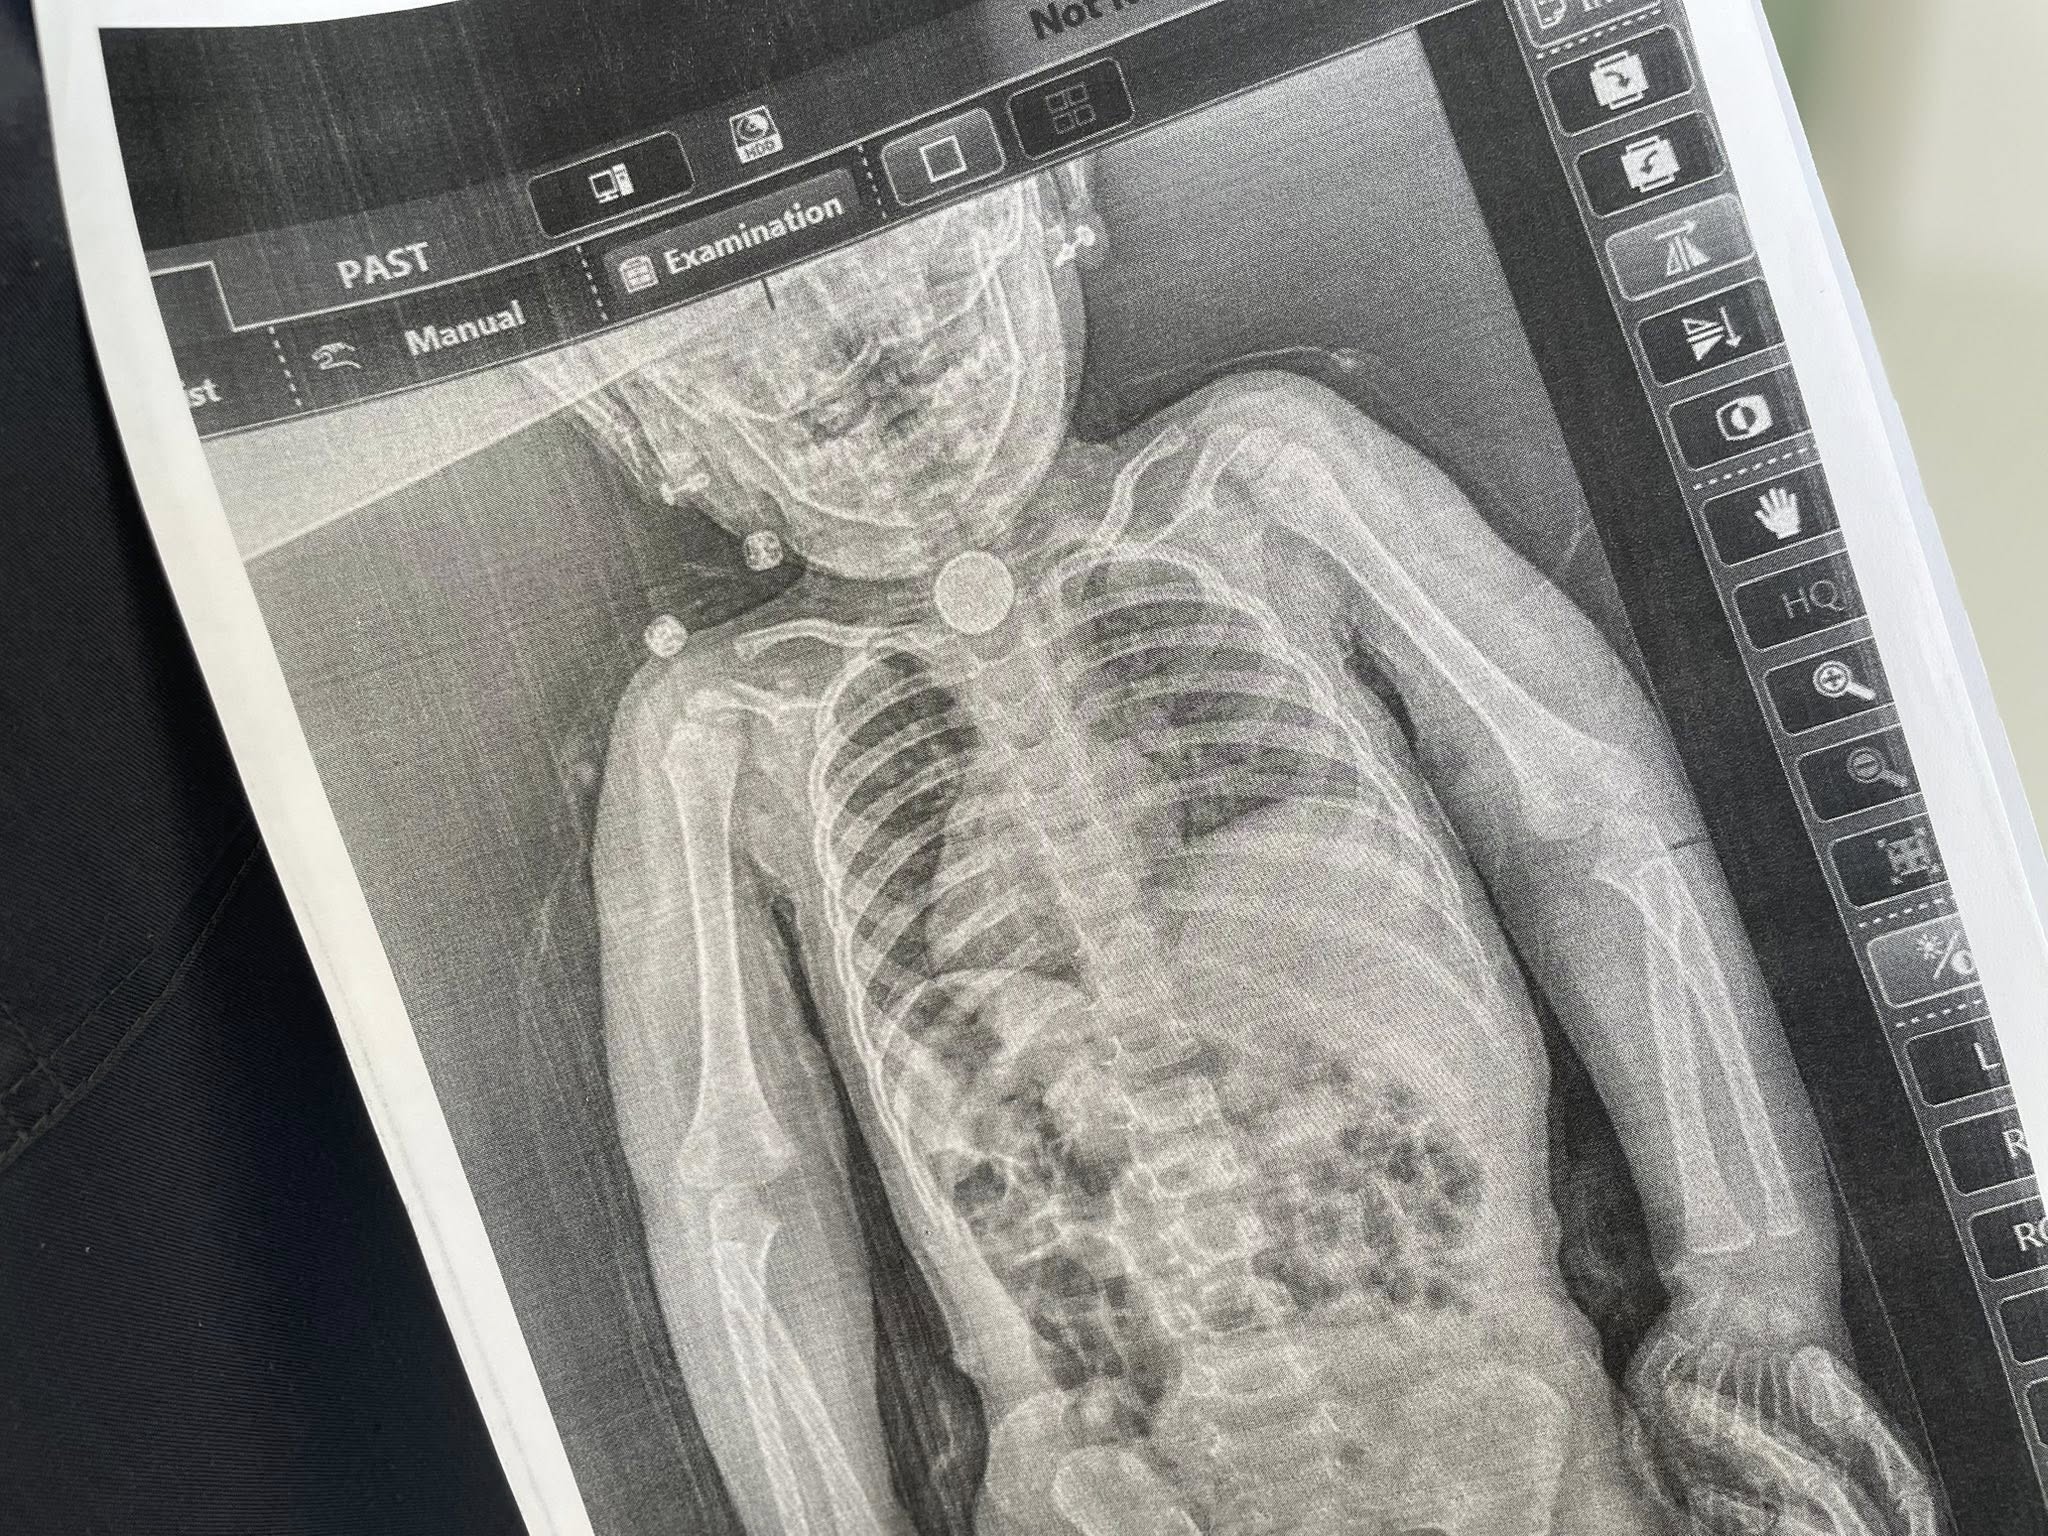

Дополнительное обследование, включая рентген, наконец показало причину – в первом физиологическом сужении пищевода прочно застряла круглая батарейка диаметром 2,5 см.